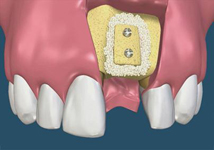

Novinkou v augmentačních metodách, kterou jako první v České republice používáme v našem zařízení je ultrazvuková metoda pomocí polylaktidové membrány - SonicWeld Rx®, kterou zavedl do implantologie v roce 2009 Dr. Dr. G.Iglhaut (Memmingen, Německo).

Jedná se o augmentační metodu při dostavbách kosti a defektech kosti horní a dolní čelisti.

Nový typ kortikální laminy (OsteoBiol) slouží k překrytí augmentačního materiálu při rozsáhlých 3D augmentacích a u velkých kostních

defektů. Jedná se o bovinní typ kortikální kosti.

SonicWeld Rx